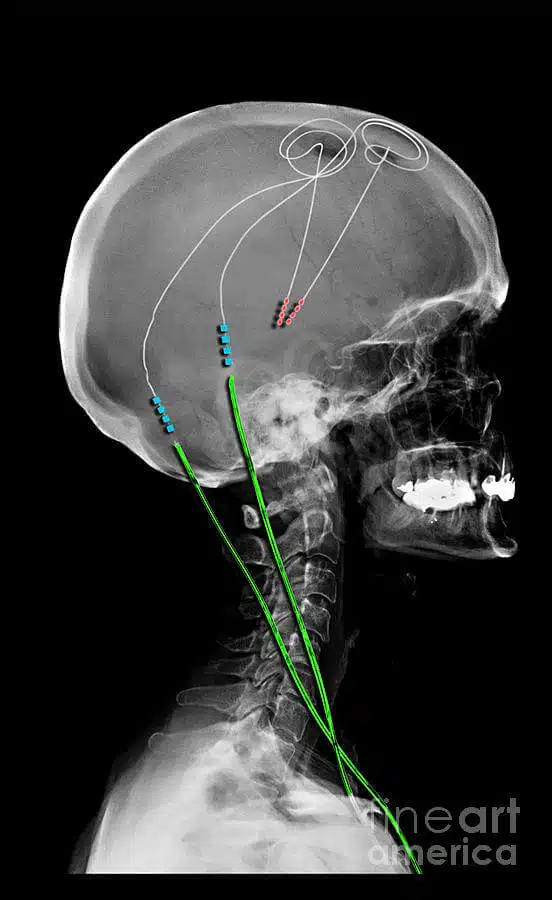

التحفيز العميق للدماغ (DBS) لعلاج مرض باركنسون هی تقنية طبية تتضمن وضع أقطاب كهربائية أو موصلات في الدماغ ، والتي ترسل نبضات كهربائية لتنظیم النبضات الغير طبيعية. يتكون هذا النهج من أربعة أجزاء:

- وصلات تنتهي بأقطاب كهربائية يتم زرعها في الدماغ

- مولّد النبض الكهربائي أو المحفز العصبي وهو جهاز صغير يشبه جهاز الناظمة القلبية

- اطالات المحفز العصبي

- مشغل كمبيوتر محمول لضبط النبضات الكهربائية وتعديل بيانات جهاز التحفيز العصبي